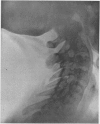

SPONDYLITIS DEFORMANS